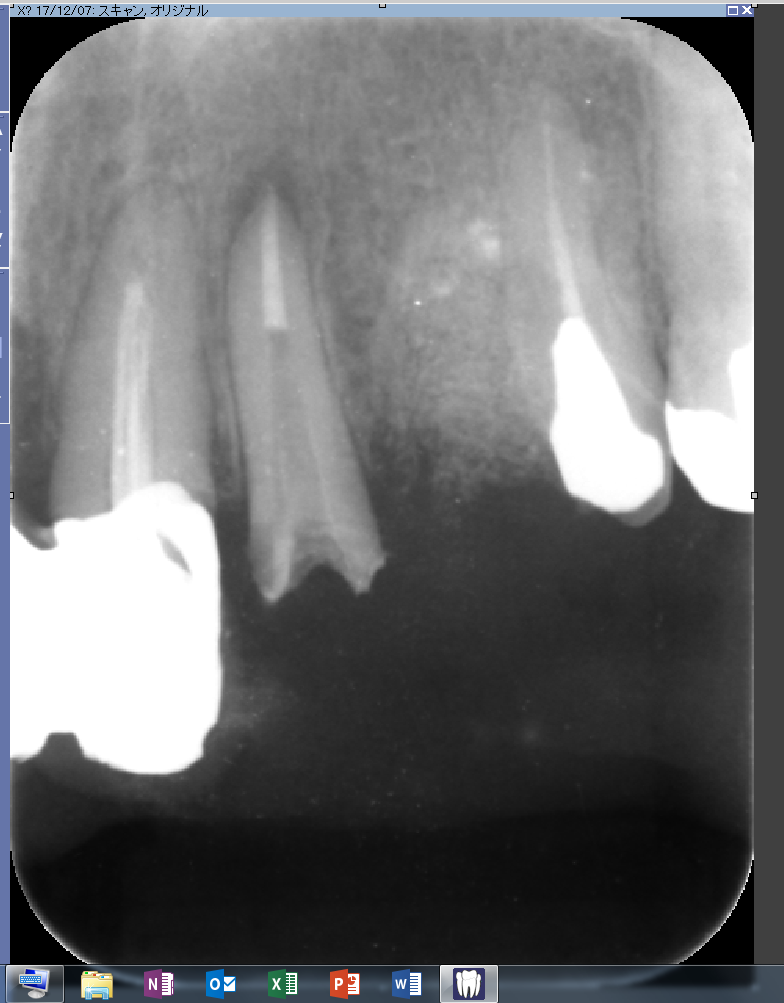

では本日の精密根管治療の御紹介

本日は2回目の来院。前回の症状も消えていました。

根尖が大きいケースではMTAセメントで根充。問題ありません。